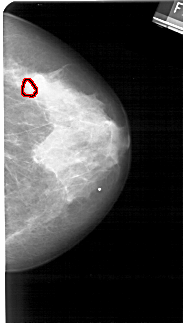

A_1270_1.LEFT_MLO

LEFT_MLO LINES 5356 PIXELS_PER_LINE 2881 BITS_PER_PIXEL 12 RESOLUTION 43.5 NON_OVERLAY

RIGHT_MLO LINES 5491 PIXELS_PER_LINE 2791 BITS_PER_PIXEL 12 RESOLUTION 43.5 OVERLAY

FILE: A_1270_1.RIGHT_MLO.OVERLAY

TOTAL_ABNORMALITIES 1

ABNORMALITY 1

LESION_TYPE CALCIFICATION TYPE PLEOMORPHIC DISTRIBUTION CLUSTERED

ASSESSMENT 4

SUBTLETY 4

PATHOLOGY BENIGN

TOTAL_OUTLINES 1

BOUNDARY